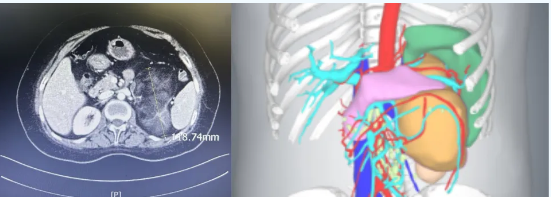

图片患者陈某CT

17a-羟化酶缺陷症是一种由常染色体隐性遗传引起的性激素异常相关肾上腺外科疾病,其临床表现主要包括肾上腺来源性激素不足、双侧肾上腺皮质增生以及高血压等症状。患者陈某在10年前被确诊为17a-羟化酶缺陷症。去年,她在其他医院被检查出患有双侧肾上腺肿瘤,其左侧肿瘤直径达到了13厘米,并伴有较高的血压。由于手术难度较大且风险较高,该医院建议她转至其他医疗机构进行治疗。面对巨大的思想压力,陈某怀揣着最后的希望,来到了自治区人民医院内分泌科就诊。在这里,主任郭艳英的团队与协和医院的张玉石教授共同为她进行了会诊,经过仔细的评估和讨论,最终建议她接受左肾上腺肿瘤的切除手术。